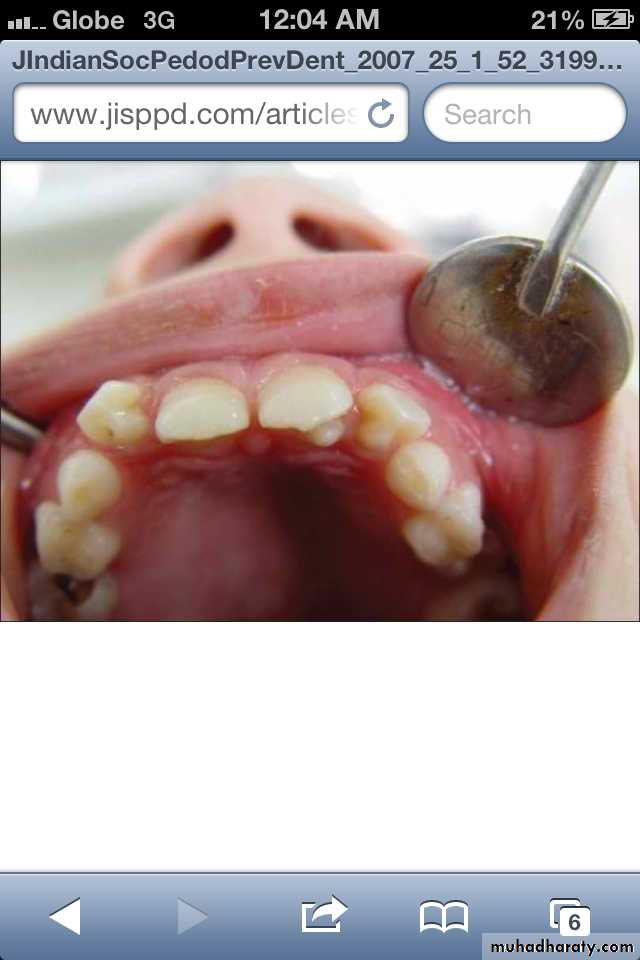

*In contrast to the dens in dente, Dens Evaginatus is the result of an outfolding of the enamel organ, involving an extra cusp or tubercle that protrudes from the tooth.

*Premolars are more likely to be affected than any other tooth.

*Located on occlusal surface between buccal & lingual cusps of premolars.It may be unilateral or bilateral.

*CAUSE:is unknown, but is thought to be a result of genetics or a disruption of the tooth during formation.

*TREATMENT:This condition requires monitoring as the tooth can lose its blood and nerve supply as a result,and may need root canal treatment.

Dens Evaginatus ( Leong's premolar)